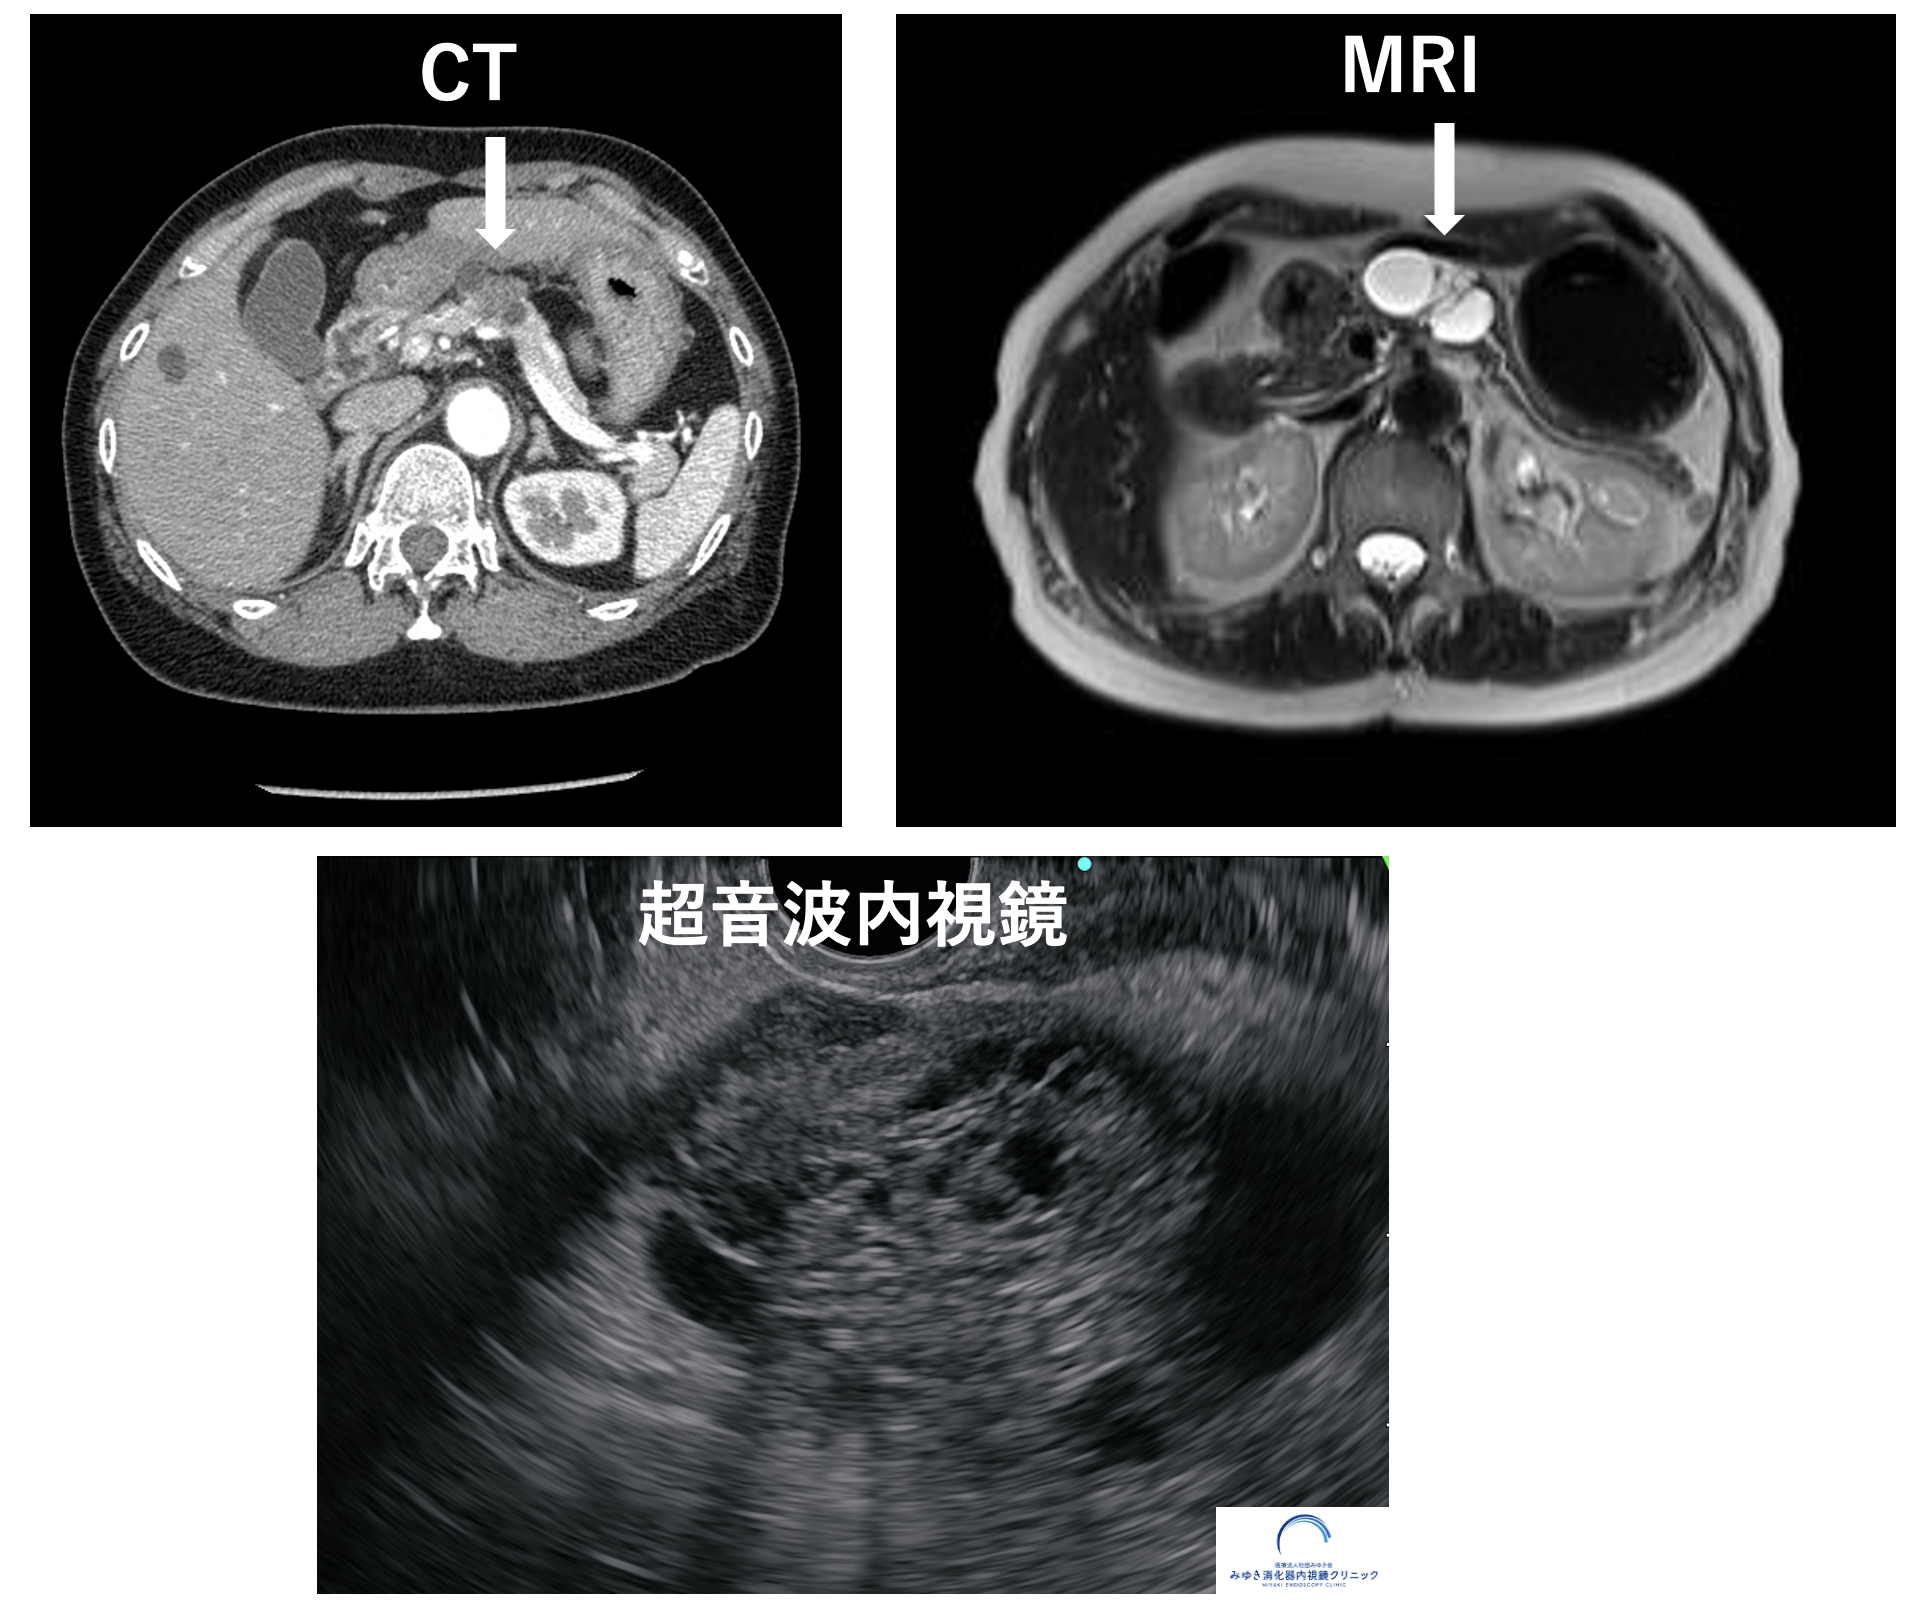

<ステージ1膵がん>

膵嚢胞、膵管拡張精査目的に当院で超音波内視鏡を行いました。膵臓に10mmの腫瘤を認めたため、超音波内視鏡穿刺吸引法(EUS-FNA)を施行し、膵がんと診断しました。CTとMRIではこの腫瘤は同定できませんでした。